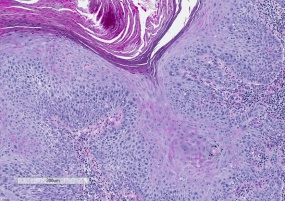

Pathology

Histologically, hyperkeratosis, parakeratosis, dyskeratosis, and solar elastosis are seen. Cellular atypia may be present, with increased nuclear-to-cytoplasmic ratio, pleomorphism, or nuclear hyperchromatism. Exposure to these forms of radiation leads to a complex series of genetic events which eventually lead to the the proliferation of squamous epithelial cells and dysplastic changes in the skin that are characteristic of actinic keratosis.